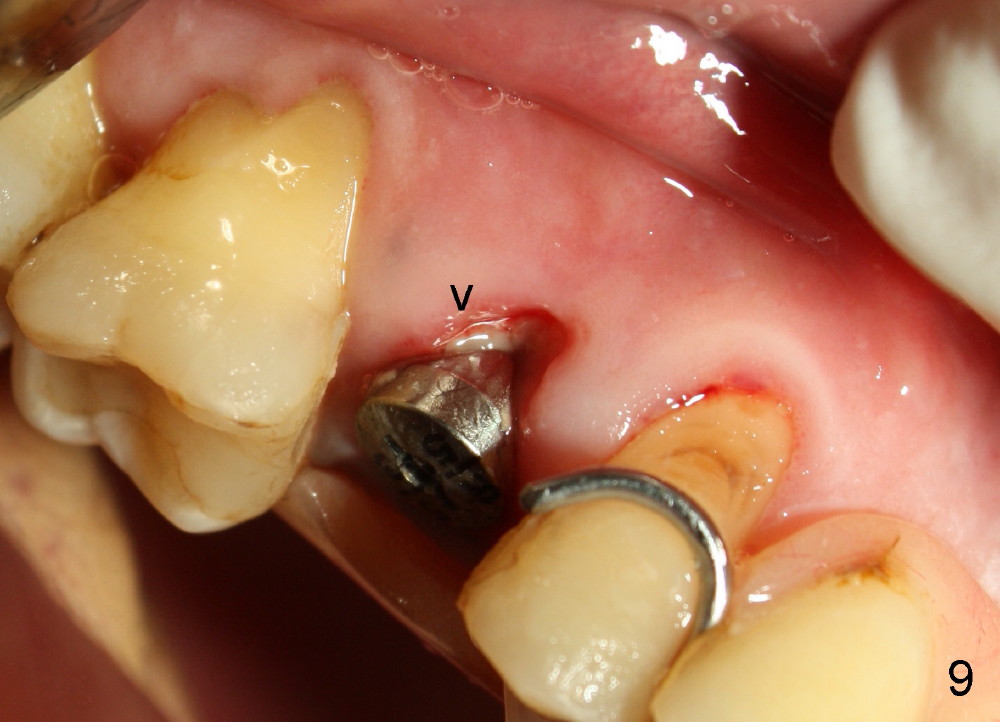

By 2 weeks postop, there is granulation tissue formation around the buccal aspect of the implant/abutment (Fig.9 arrowhead). The wound (gingival recession) appears to shrink (as compared to Fig.7,8). The patient feels great and wonders why no crown is fabricated. Once the granulation tissue is mature, a provisional crown will be made. The reason that no immediate provisional is provided in this case is that there are several missing teeth and that the implant may be overloaded. If there is no overloading issue, immediate provisional is preferred to the membrane. The provisional can provide with more secure coverage over the bone graft.